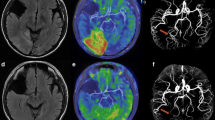

Brain imaging was performed in the acute phase (median 0 days after symptom onset, interquartile range 0–1) and exhibited symmetric high signal intensity lesions in the medial thalamus, MB, hypothalamus, fornix, tectum, inferior colliculus, or medial vestibular nuclei on FLAIR or DWI (Table 1). Five patients had abnormalities in the hypothalamus and tectum, and four patients exhibited an abnormality in the medial thalamus. Five patients underwent contrast-enhanced T1WI and showed abnormality in the area of on FLAIR or DWI. Interestingly, all lesions on FLAIR, DWI, or T1-contrast imaging were identified as hyperintensity on ASL-PWI (sensitivity 100%) (Fig. 1, Supplemental Table 1). The average measured CBF using ASL-PWI was different among the affected anatomical structures (from 70.3 mL/100 g/min in the medial thalamus to 190.0 mL/100 g/min in the hypothalamus). Indeed, CBFnormalized ranged from 2.5 (fornix) to 5.5 (tectum and medial vestibular nuclei) compared with frontal subcortical white matter (Supplemental Table 1).

Representative figure of the patients. Pathognomonic hyperintensity lesions were observed in the mammillary body and red nucleus (a and b, arrows, case 1); medial thalamus and fornix (c and d, arrows, case 2); tectal plate (e and f, arrows, case 7) and mammillary body (g and h, arrows, case 5). a, c, e, and f were fluid-attenuated inversion recovery imaging; b, d, f, and g were arterial spin labeling imaging

This study demonstrated that focal hyperintensity on ASL-PWI is obvious in the lesions on FLAIR, DWI, or contrast-enhanced T1WI in the acute symptomatic phase of WE. Moreover, CBF in the lesions was elevated by a factor of 2.5 to 5.5 compared with that of frontal subcortical white matter.

With recent advances in non-invasive imaging, ASL-PWI enables the identification of perturbed CBF in various clinical situations. In our study, all patients exhibited dramatic hyperintensity on ASL-PWI in vulnerable areas related to WE, including the medial thalamus, hypothalamus, tectum, or MB with 100% sensitivity. There are a few hypotheses on the mechanism of focal hyperemia in WE. In the acute phase of WE, an increase in lactate production by neurons and astrocytes was identified, which leads to endothelial dysfunction and increased production of nitric oxide [8], and may result in increased vascular permeability, vasodilation, and hyperemia [9]. Therefore, hyperperfusion or hyperemia may exist in the acute phase of WE. Consistent with this, one study reported the focal hyperemia using CT perfusion in a patient with WE who presented with acute onset confusion, dysarthria, and facial palsy [10]. In addition, an animal study using thiamine deficiency reported that focal hyperemia was evident and slowly improved over several weeks after symptom development [5]. Taken together, increased CBF is mechanistically relevant in the pathogenesis of WE, especially in the acute phase. When necrosis occurs in the chronic phase, focal hyperemia may disappear. This may partly explain the previous results of decreased CBF in WE because CBF was measured in the subacute phase.